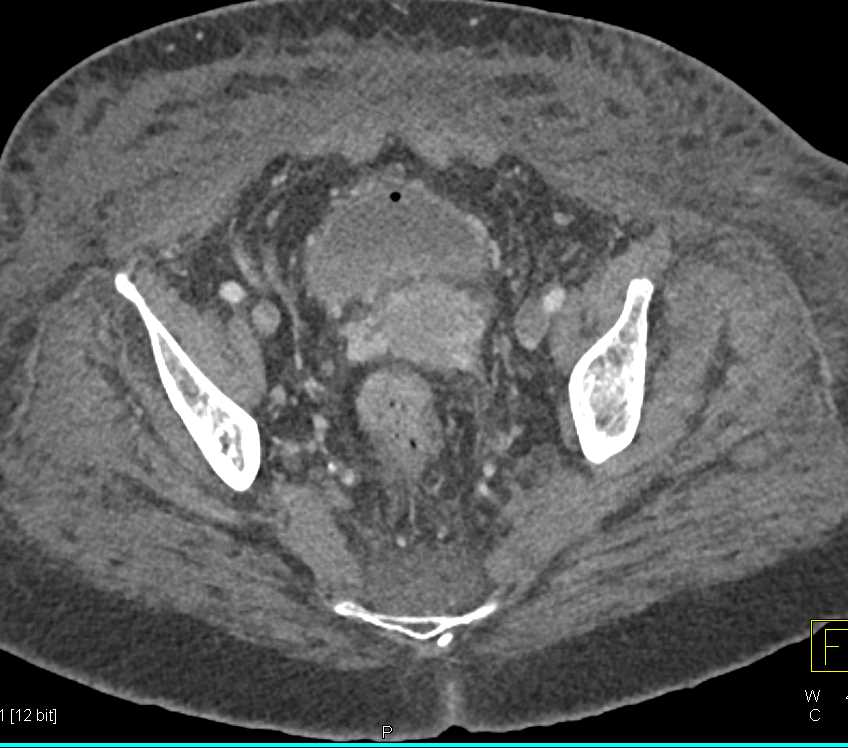

Gastric GIST Tumor with Carcinomatosis